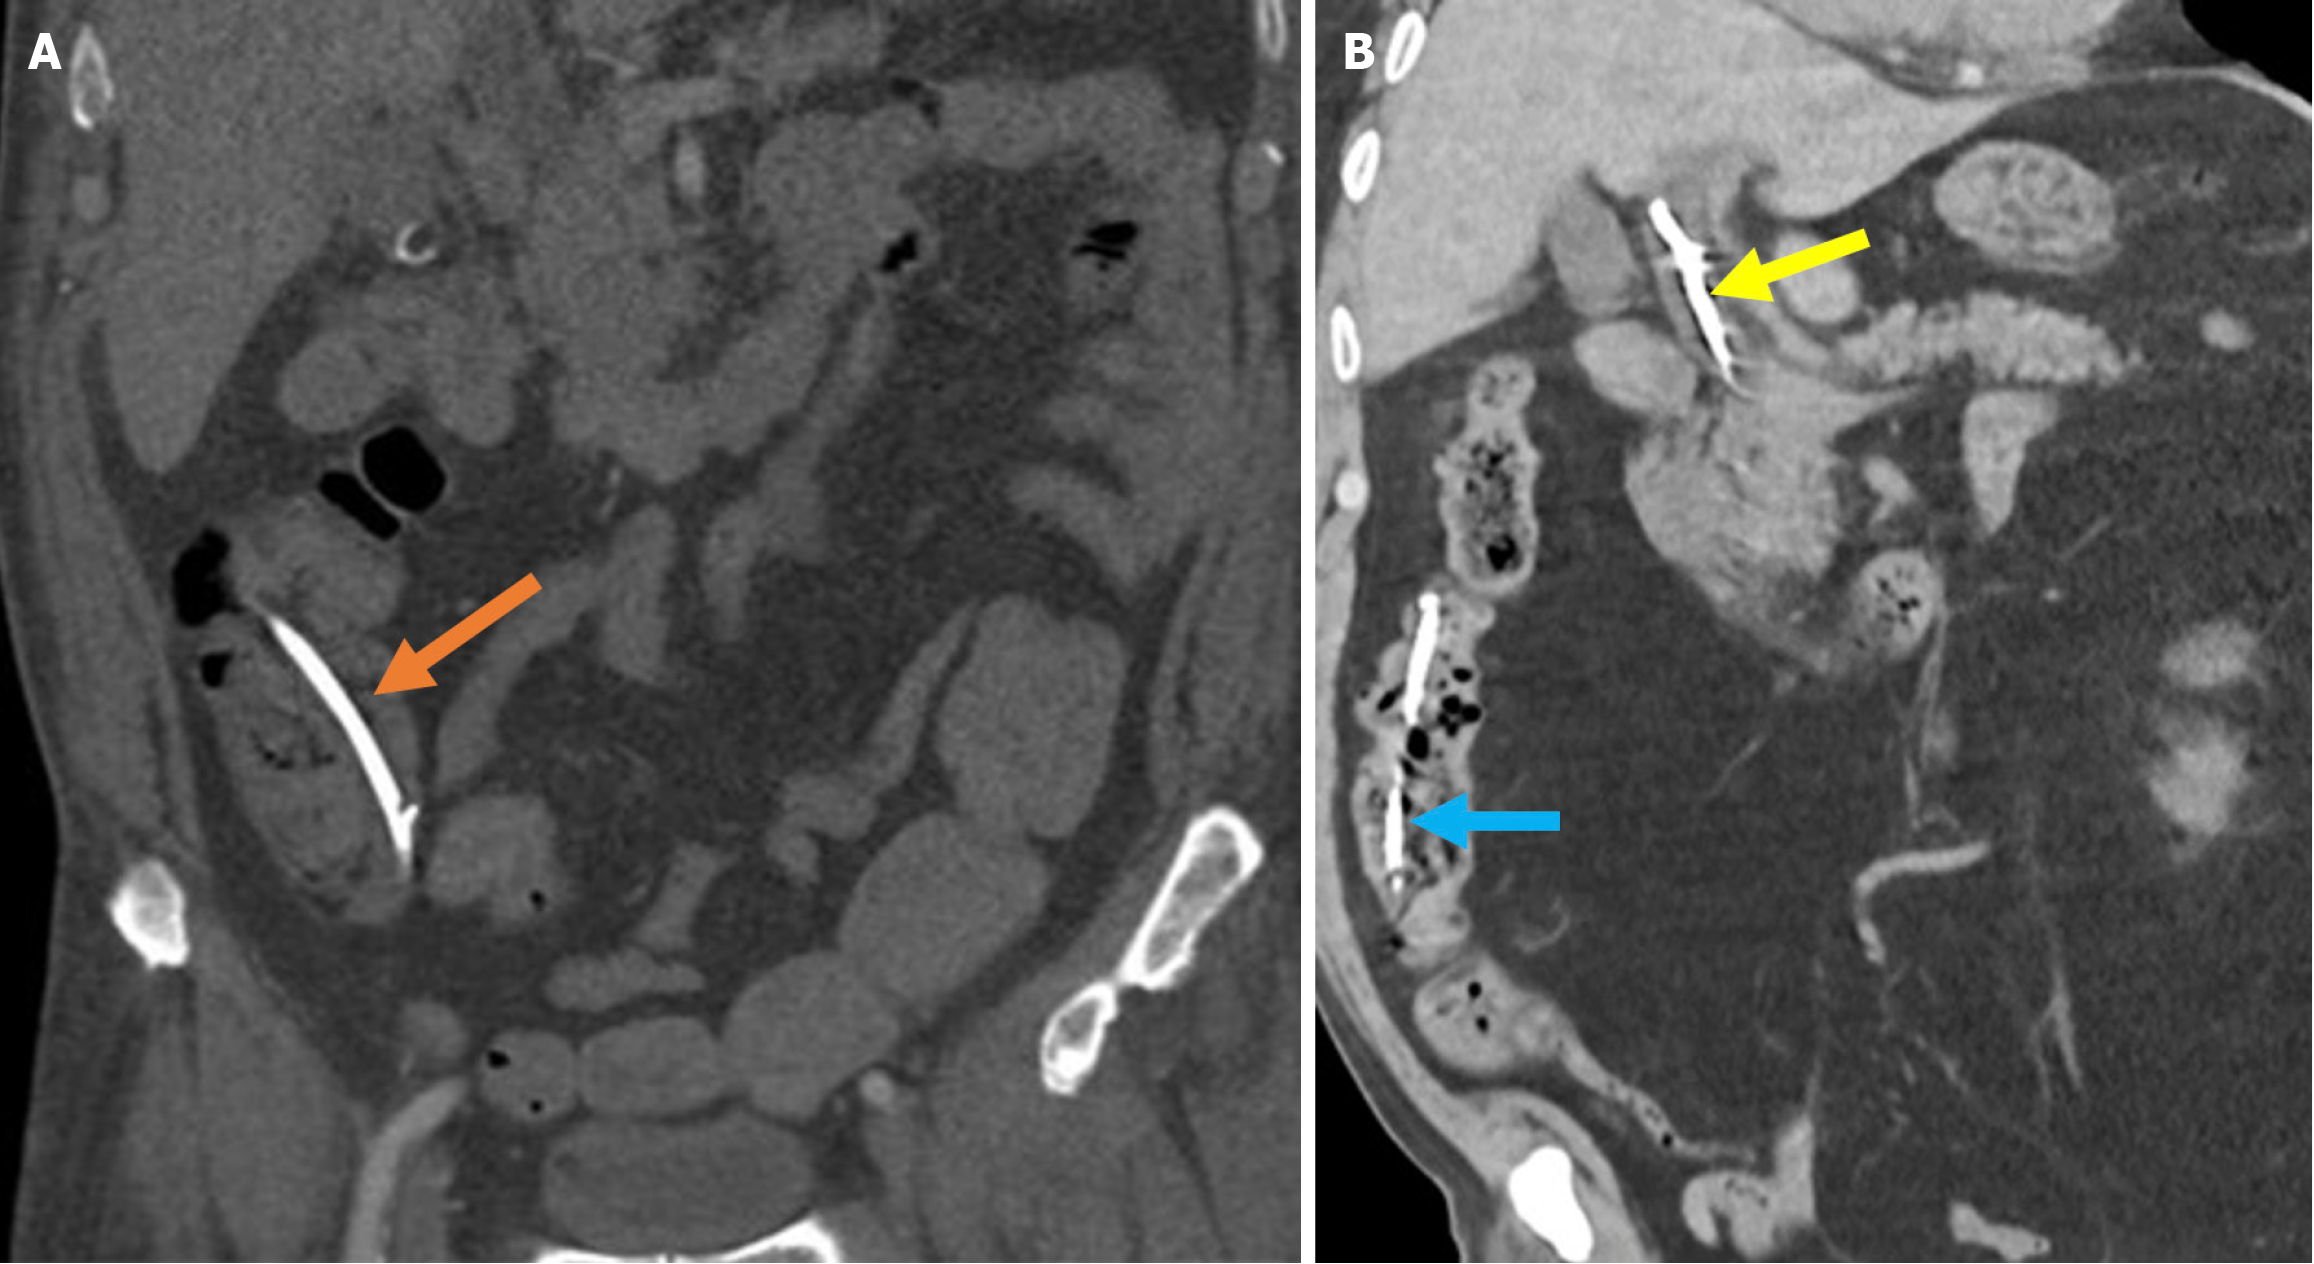

Stent fracture: A stent fracture is a rare complication that may lead to biliary obstruction and an increased risk of cholangitis if left untreated. It is commonly observed in SEMS while fractures of plastic stents are exceedingly rare. The underlying mechanism involves metal fatigue resulting from repeated bending and mechanical stress over time (Figure 19)[85,86].

Figure 19  Stent fracture. A: Posteroanterior chest radiograph; B: Contrast-enhanced coronal computed tomography scan. A 52-year-old female patient presented to the hospital 3 days after biliary stent placement via endoscopic retrograde cholangiopancreatography with complaints of abdominal pain and elevated levels of aspartate aminotransferase, alanine aminotransferase, and bilirubin. The imaging revealed a fracture of the previously placed plastic stent (yellow arrow). A repeat endoscopic retrograde cholangiopancreatography was performed to remove the fractured stent, but residual stent fragments remained within the common bile duct. The duct appeared dilated due to malfunction of the broken stent (blue arrow).

Post-sphincterotomy biliary stricture

Post-sphincterotomy biliary stricture is a rare complication. It results from fibrosis at the sphincterotomy site and can develop months to years after the procedure. Strictures located just above the duodenal wall are classified as type 1, while those situated deeper within the bile duct are type 2. In type 1 strictures, a simple extension of the sphincterotomy may be sufficient, whereas type 2 strictures often require balloon dilation. Similarly, the pancreatic duct orifice may also become stenotic following sphincterotomy, leading to recurrent episodes of pancreatitis (Figure 20)[38,68].

Figure 20  Post-sphincterotomy biliary stricture. A: Coronal T2-weighted magnetic resonance imaging; B: Fat-suppressed post-contrast T1-weighted magnetic resonance imaging showed a biliary stricture in a 40-year-old male patient with a history of endoscopic retrograde cholangiopancreatography and sphincterotomy. Focal stenosis was observed in the mid portion of the common bile duct without any associated mass lesion (yellow arrows). There was associated mural thickening of the mid-bile duct and dilatation of the intrahepatic bile ducts (blue arrows). The findings were consistent with a benign biliary stricture secondary to prior endoscopic retrograde cholangiopancreatography.